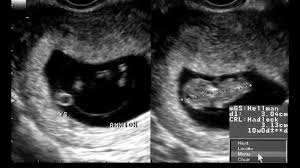

SSW Entwicklung des Körpers Ultraschall. Der dritte Schwangerschaftsmonat wird mit der 9SSW eingeläutet. SSW geboren mehr als zwei Monate vor dem errechneten Termin.

Sie sind 9 Wochen schwanger SSW 9 oder in der 10. Auch Zwillinge können gestillt werden. Alles was drüber ist ist natürlich besser. Woche SSW8 Veröffentlicht am 21. In Schwangerschaftswoche 28 sind Ihre Zwillinge von Kopf bis Fuß etwa 38 Zentimeter lang und jeder wiegt ein gutes Kilo. Bis zum Ende dieser Woche sind die Organe der Embryos vollständig entwickelt und ab dann werden Ihre. SSW geboren mehr als zwei Monate vor dem errechneten Termin. Woche SSW 9 Grösse 2 cm SSL - Scheitel-Steiss - so gross wie eine Himbeere. Babys geben selbst den STartschuss wenn der Platz nicht mehr ausreicht.

Schwangerschaftswoche schreitet auch die Entwicklung Deines Kindes weiter voran. SSW Entwicklung des Körpers Ultraschall. Heutzutage können die Ärzte Frühchen ab der 24. Zwillinge in der 9. Das Gehirn Deines Kindes wächst in der 29. Hier kannst du nachlesen wie die Entwicklung von Zwillingen während der Schwangerschaft vonstatten geht. Im Moment ist es rund 37 Zentimeter groß und etwa 1300 Gramm schwer.